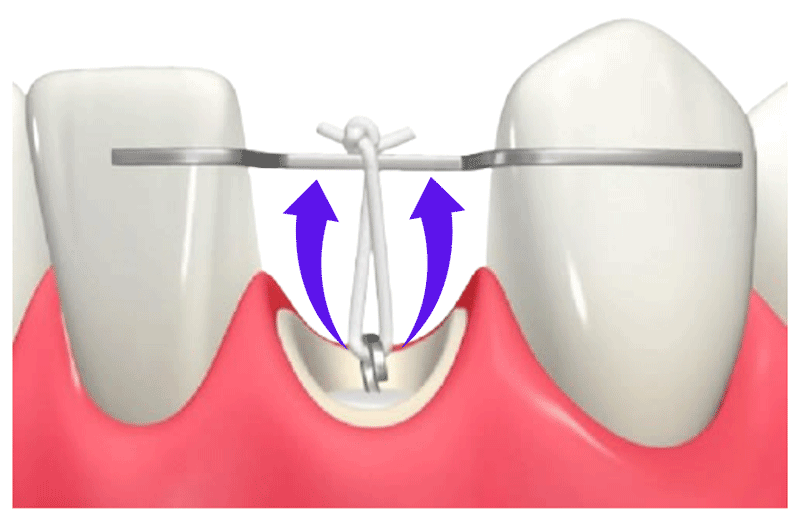

②矯正装置の装着

ブラケットやワイヤーで力を加える

上の図のように歯根にワイヤーを埋め込み、仮歯にもあるワイヤーとゴムで連結し引っ張る。